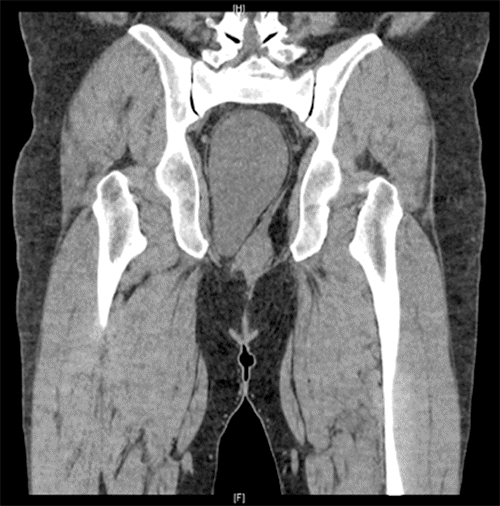

The patient is a 66-year-old White male with a medical history of morbid obesity who presented to the outpatient surgery clinic with swelling to the right gluteal area. He demonstrated a 10 × 12 cm soft tissue mass on physical examination along the right inferior gluteal fold. Though the lesion was clinically consistent with a lipoma, applying gentle pressure to the mass resulted in referred pain and pressure within the abdomen. There was no cough impulse, but movement was noticed in the abdomen when reducing the swelling. The differential diagnosis was expanded to include a soft tissue lesion extending from the pelvis and/or a hernia defect. Given the patient's habitus and equivocal physical exam findings, an ultrasound was performed, which noted a hypoechogenic area in the gluteal fold region appearing to herniate through a defect with coughing followed by spontaneous reduction. (Figure 1A) The contralateral region was imaged without similar findings, raising the suspicion of a gluteal hernia versus a gluteal lipoma. Due to poor compliance, the patient was initially lost to follow-up but returned to the clinic within a year with complaints of a symptomatic increase in the size of the swelling. A CT scan of the pelvis demonstrated a large well-circumscribed oval mass measuring 11.9 × 7.5 × 14.9 cm in the deep pelvis posterior and lateral to the rectosigmoid colon extending into the ischiorectal fossa on the right side. The internal density of the mass was 17 Hounsfield units. It appeared to be a cystic fluid collection with  possible blood or proteinaceous debris (Figure 1B and Figure 1C).

B) CT imaging of pelvis showed large, well-circumscribed oval mass in deep pelvis posterior and lateral to rectosigmoid, which extended into right ischiorectal fossa. Measured 11.9 × 7.5 × 14.9 cm. Internal density of mass was 17 Hounsfield units.

C) CT imaging of pelvis showed large, well-circumscribed oval mass in deep pelvis posterior and lateral to rectosigmoid, which extended into right ischiorectal fossa. Measured 11.9 × 7.5 × 14.9 cm. Internal density of mass was 17 Hounsfield units.